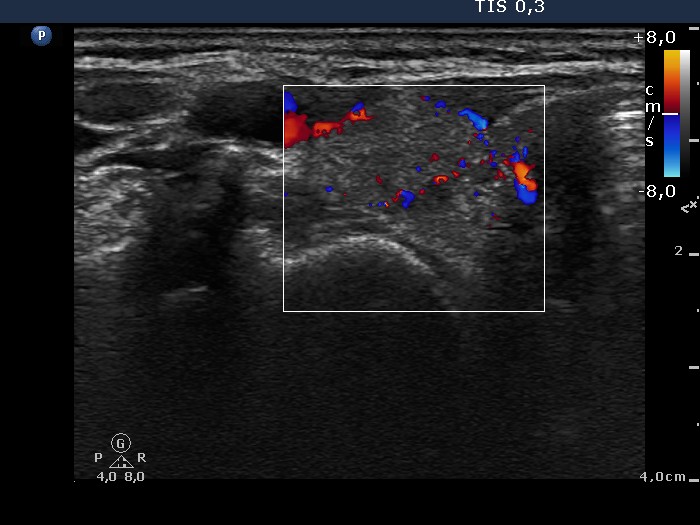

Ultrasonography: the thyroids were moderately hypoechogenic. There was an echonormal, inhomogeneous mass next to the upper pole of the right lobe. Muscle fibers were found between the thyroid and the hyperechogenic lesion. The latter displayed type 2 vascular pattern.